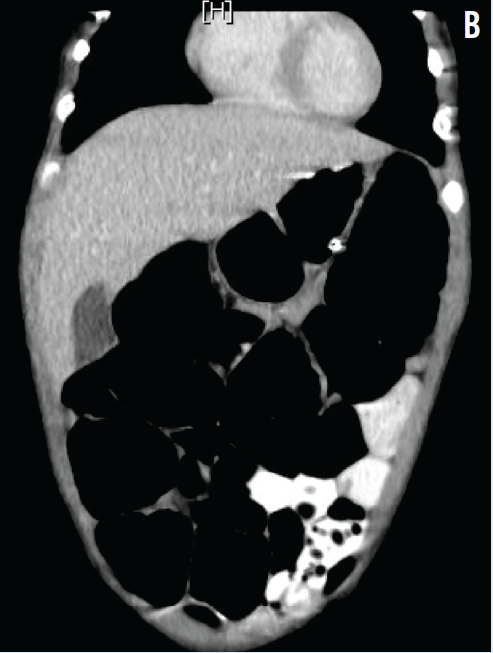

On the fourth day of hospitalization, the boy had an episode of emesis. An abdominal computed tomography scan visualized the dilated bowel loops and confirmed the lack of mechanical obstruction (Figure B). Stool samples were sent for pH testing, reducing substances, culture, Clostridium difficile DNA amplification, and a rotavirus enzyme immunoassay. The patient was started empirically on metronidazole for possible bacterial overgrowth.